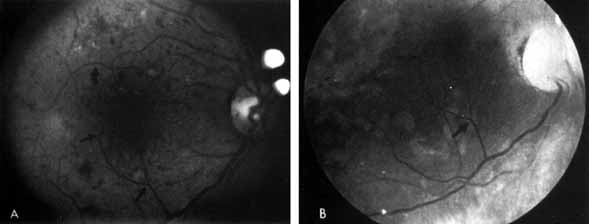

Although microaneurysms are the first ophthalmoscopically detectable change in diabetic retinopathy, the earliest abnormalities seen histopathologically are thickening of the capillary basement membrane1,2 and pericyte dropout.3,4 Pericytes are mesothelial cells that surround and support the retinal capillary endothelial cells. Normally there is one pericyte per endothelial cell. In people with diabetes, however, the pericytes die off and are decreased in number (Fig. 1). Their absence weakens the capillaries and permits thin-walled dilatations, called microaneurysms, to develop. Later, endothelial cells proliferate and lay down layers of basement membrane material. Fibrin may accumulate within the microaneurysm along with erythrocytes, and the lumen of the microaneurysm may become occluded (Fig. 2). Initially, most microaneurysms are on the venous side of the capillaries, but later they are seen on the arterial side as well. Clinically, they appear as small red dots (Fig. 3). Despite the multiple layers of basement membrane, microaneurysms are permeable to water and large molecules, allowing the transudation of fluid and lipid into the retina.

Fig. 1 A. Trypsin digest preparation of early background retinopathy. Normal retinal capillaries, with one pericyte (closed arrows) per endothelial cell (open arrows). B. Retinal capillary of a patient with diabetes with necrotic pericytes (arrows). (Courtesy of Dr. Myron Yanoff)